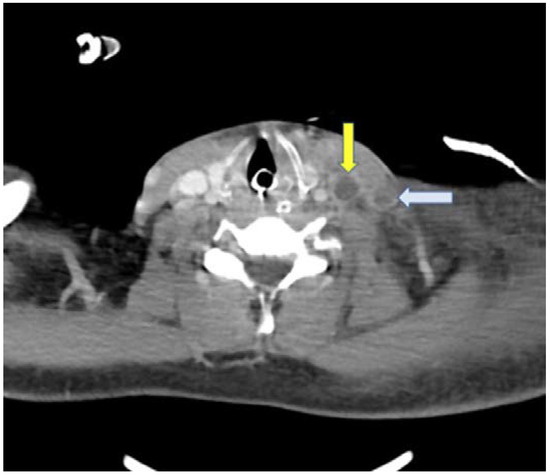

A CT scan of the thorax showed multiple pulmonary nodules some of which showed central cavitation distributed through the lung parenchyma corresponding to septic emboli with areas of ground-glass pattern (Figure 1).

Figure 1. Axial view of the chest CT scan showing multiple areas affected with pulmonary nodules, some of which show central cavitation and a consolidation image.